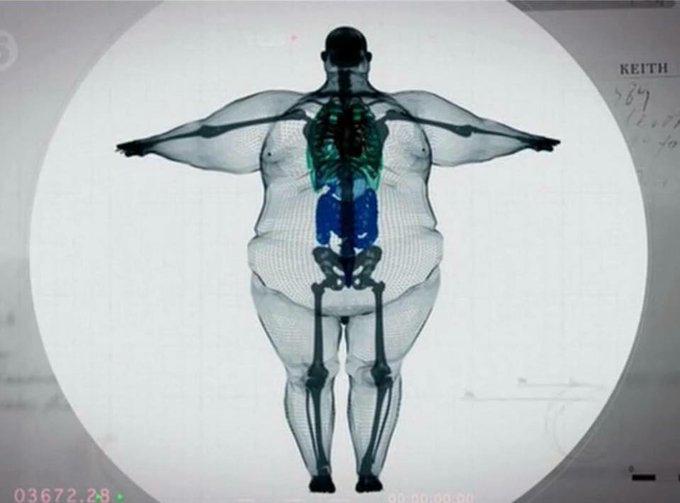

And This Is What It Looks Like With Those Unwanted Dangerous and Cancer-Causing Fat You Have Now.

In fact, research considers it an ‘active fat’.

Then it is important for you to pay attention to the following image below…

The image below shows you the layers of fat in your belly.

But when you look closely especially on the red arrow.

You’ll see thick layers of skin attached to your belly and almost close to your abdomen.

Now, what most people don’t know is that those layers are considered ‘active’ fat.

Because they more than ever are a part of your body.

Which is why they are hard to lose.

But what makes this layer of skin interesting is that…

They can collapse and also expand.